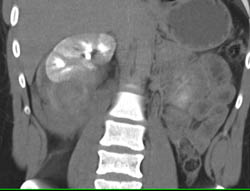

Renal Cell Carcinoma